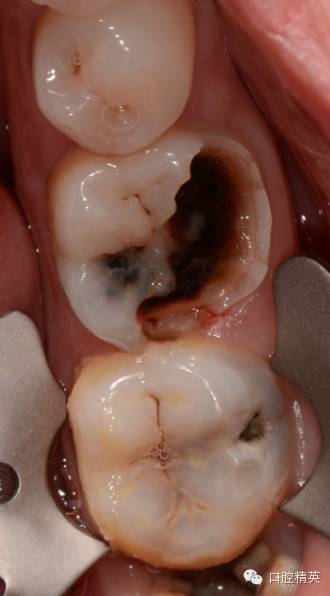

患者女性,自诉左下后牙冷热不适两年多,昨夜疼痛加重,冷热水加重,疼痛累及头部及耳部,影响睡眠,今来诊,求治。

查:36颊he面及远中大面积龋坏,色黑质硬,探敏感,未探及穿髓孔,冷测持续性疼痛,扣无不适,不松,龈正常,对侧同名牙电活力测试值38,36电测牙髓活力值11。37颊侧龋,探敏感,未探及穿髓口,冷测一过性疼痛,扣无不适,不松,龈正常。

诊断:36慢性牙髓炎急性发作,37深龋

处:必兰阻滞麻醉下,36一次性根充,37树脂嵌体修复

36,37均有龋坏,且冷测敏感,很多时候我会使用牙髓电活力测试仪来判断牙髓状态,尽可能减少出现误诊,因为这种不可逆的操作,一旦出现误诊,对患者,对医生都是极大的痛苦。所以尽可能多种方法反复测试,如果实在找不到原因,时间也是一种方法。

颊侧龋坏较大,已经接近齐龈,于是树脂临时假壁修补,帮助橡皮障固定,也增加冲洗液容纳量

先清理干净准备做假壁区域的腐质,避免树脂沾接不牢在上橡皮障的时候假壁脱落,也避免漏液。